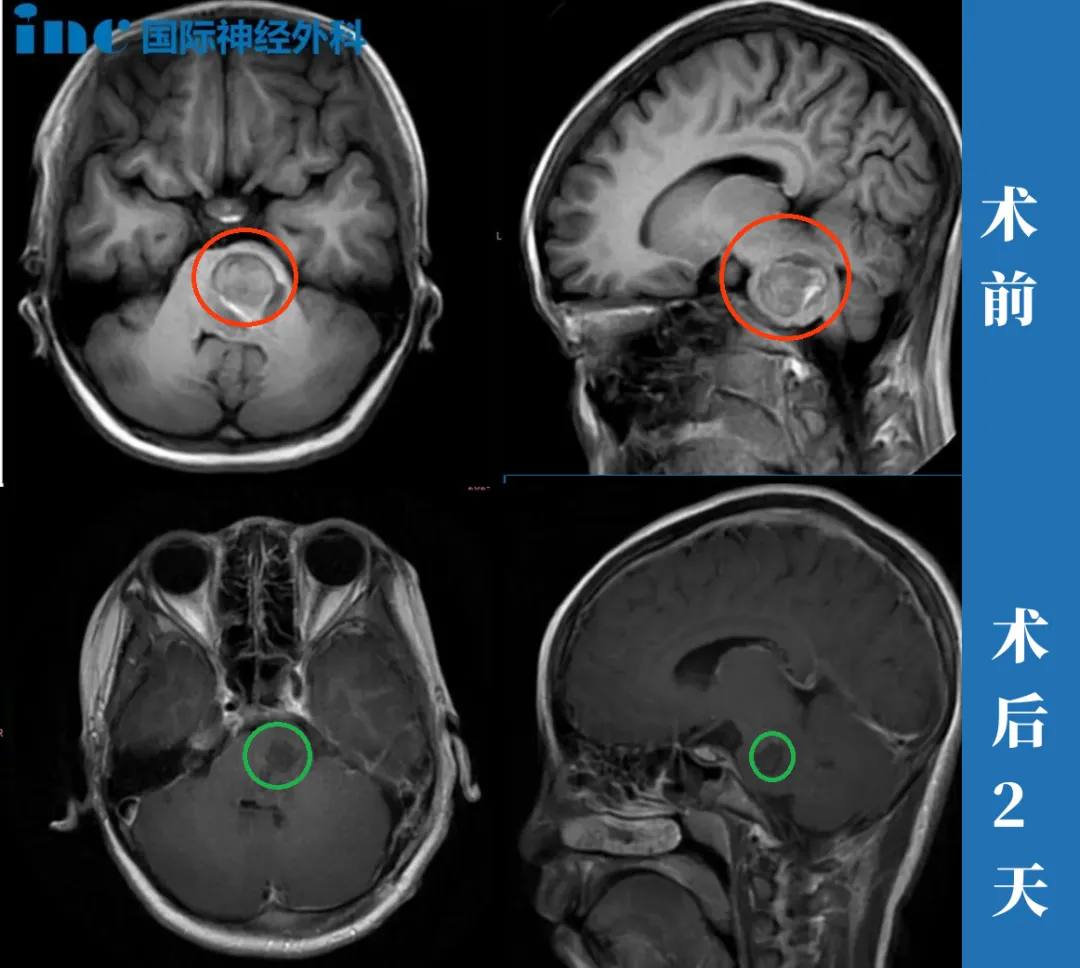

颅咽管瘤患者采访

7岁男孩—颅咽管瘤

“肿瘤本身的特点,它会压迫那个周围神经各方面的,与其到了后面更难做的情况下去做,还不如先把它做掉。顾虑其实就是两个,一个是垂体柄的保留,二个就是切除率。

他没住ICU,当天就出来了。巴教授出来的时候说:Perfect!我一听就激动得不得了。另外一个医生在旁边说,垂体柄保留的很好,我就觉得就很放心。这个手术是成功的,我觉得他真的是蛮好的,我们真的蛮幸运的。”